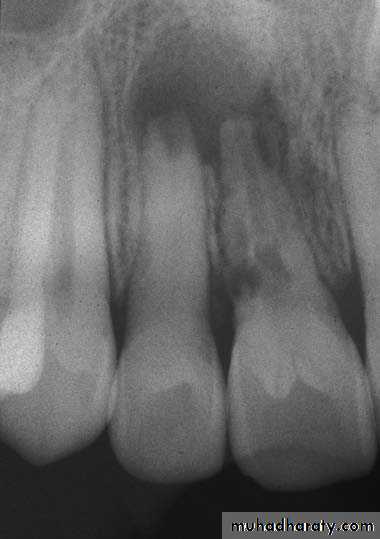

Radiographs IMPORTANCE

Provides information on the extent of caries in to the pulpNo. of root canals and accessories

The course & shape of the canals

Length of the root

CalcificationsResorptions

PDL status8. Nature of periapical area & alveolar bone

9. Root fractures10. Differentiation of pathosis

11. Location of perforations12. Post obturation evaluation

13. Evaluate healing after RCT

14. Medico legal recordsLimitations1-2 D image of 3D object

• State of pulpal health can not be ascertained

• P/A pathology is evident only after much destruction(33%)• Vertical root fracture can not be diagnosed

• Bony trabculae misinterpreted for horizontal root #

• Extend of caries is usually less than the actual extent as is true for P/A pathology

Anatomic structure can mimic P.A. pathology